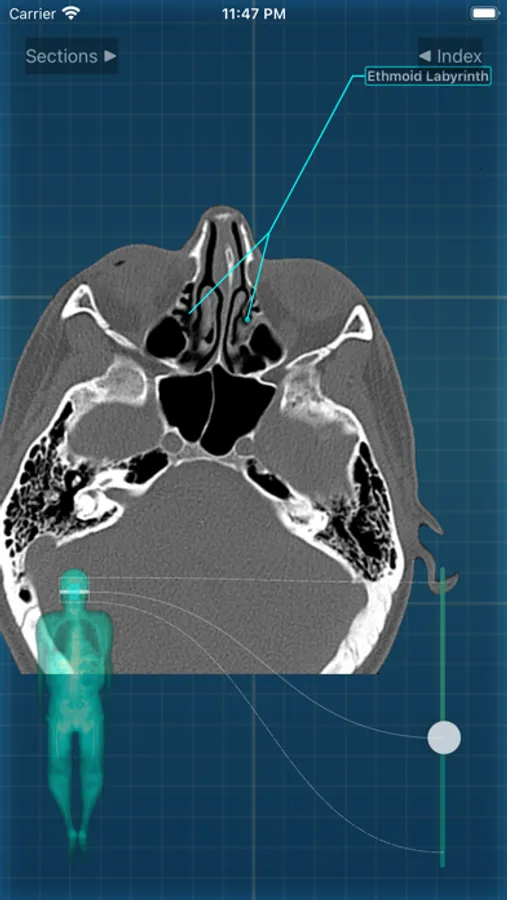

X-Anatomy is a transaxial cross-sectional human anatomy interactive medical imaging atlas using CT images, designed for medical professionals & all students of anatomy.

* Includes hundreds of images from actual human patient body scans.

* Use the intuitive BODY LOCALIZER to show you where you are as you scroll through the body, as well as the general region of the anatomic structure

INCLUDED body section modules cover the major body sections from head to pelvis: CT Brain, CT Neck, CT Sinuses, CT Chest, CT Lungs, CT Abdomen & Male Pelvis, CT Abdomen & Female Pelvis.